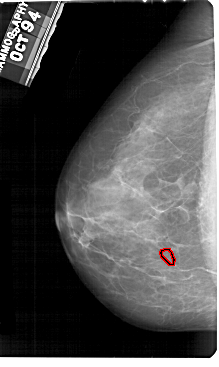

A_1945_1.LEFT_CC

LEFT_CC LINES 5491 PIXELS_PER_LINE 3271 BITS_PER_PIXEL 12 RESOLUTION 43.5 OVERLAY

FILE: A_1945_1.LEFT_CC.OVERLAY

TOTAL_ABNORMALITIES 1

ABNORMALITY 1

LESION_TYPE CALCIFICATION TYPE PLEOMORPHIC DISTRIBUTION CLUSTERED

ASSESSMENT 4

SUBTLETY 2

PATHOLOGY BENIGN

TOTAL_OUTLINES 1

BOUNDARY